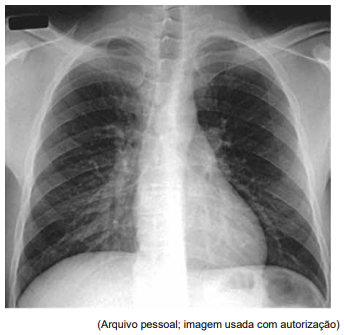

Homem de 53 anos refere quadro de febre e dispneia

progressiva há uma semana. Ele tem infecção pelo HIV,

mas abandonou o tratamento há cinco anos. Não se sabe

a contagem recente de linfócitos CD4 ou a carga viral do

HIV. A gasometria arterial revela uma PaO2

de 51 mmHg

em ar ambiente. A radiografia de tórax é mostrada a

seguir:

O lavado broncoalveolar é positivo para material com coloração de prata metenamina.

Considerando a principal hipótese diagnóstica, constitui o tratamento antimicrobiano mais adequado: